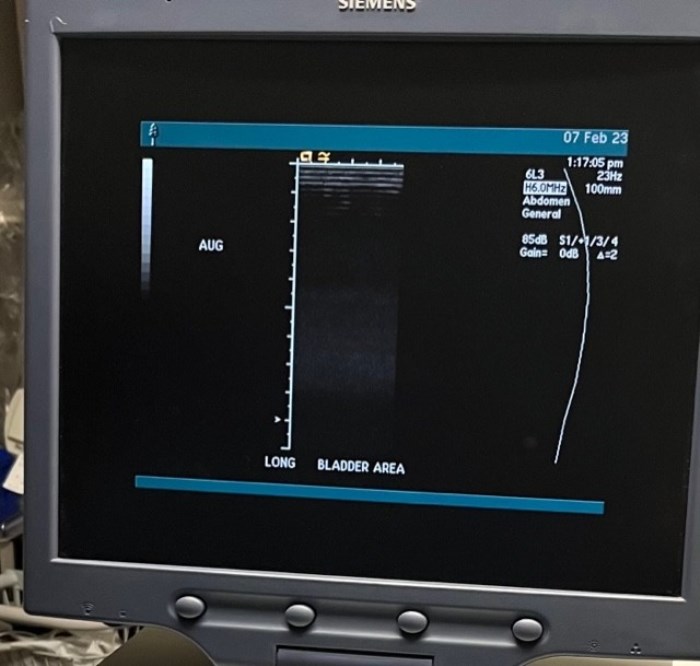

Siemens Sequioa Ultrasound

Pre-owned. In good working condition. Shown as is. Siemens Sequoia Ultrasound. DOM: 2006

Probes: 15L8w, 4V1, 10V4, 6L3, 4C1